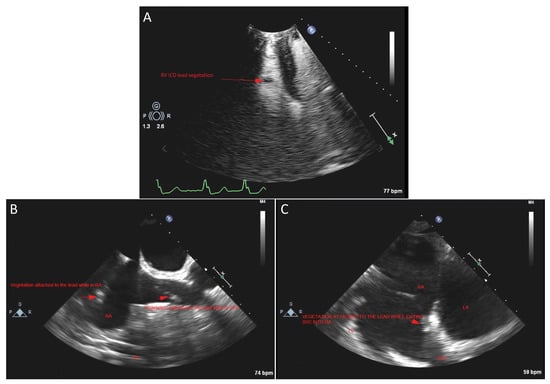

- Manning, W.J.; Weintraub, R.M.; Waksmonski, C.A.; Haering, J.M.; Rooney, P.S.; Maslow, A.D.; Johnson, R.G.; Douglas, P.S. Accuracy of transesophageal echocardiography for identifying left atrial thrombi. A prospective, intraoperative study. Ann. Intern. Med. 1995, 123, 817–822. [Google Scholar] [CrossRef] [PubMed]

- Durmaz, E.; Karpuz, M.H.; Bilgehan, K.; Ikitimur, B.; Ozmen, E.; Ebren, C.; Polat, F.; Koca, D.; Tokdil, K.O.; Kandemirli, S.G.; et al. Left atrial thrombus in patients with atrial fibrillation and under oral anticoagulant therapy; 3-D transesophageal echocardiographic study. Int. J. Cardiovasc. Imaging 2020, 36, 1097–1103. [Google Scholar] [CrossRef] [PubMed]

- Hubbard, E.; Wise, E.; Hubbard, B.; Girard, S.; Kong, B.; Moudgal, V. Tucked away: An infected thrombus. Am. J. Med. 2016, 129, 576–579. [Google Scholar] [CrossRef] [Green Version]